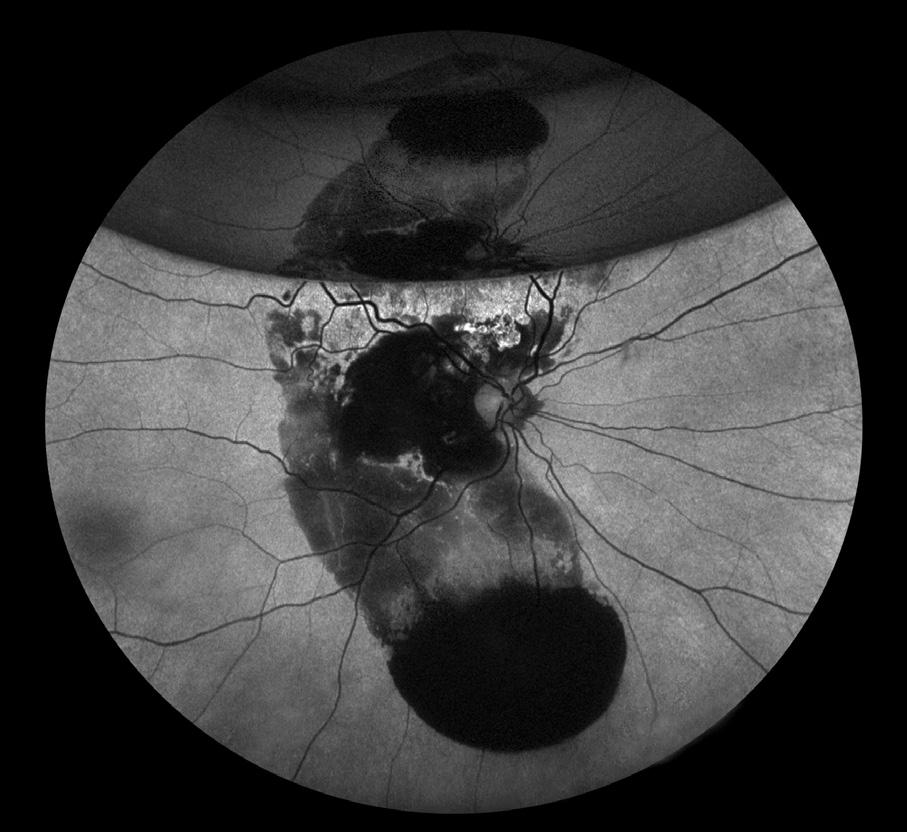

Fluorescein Angiography

PDR with VH

Bradley Stern, CRA, OCT-C

Henry Ford Health System

Detroit, Michigan

PDR (AV Phase)